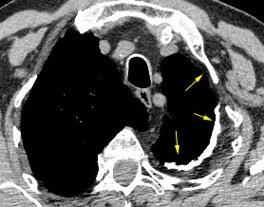

Empiema pleural izquierdo. Absceso del LID. Espondilodiscitis D11-D12.

Potsios C et al. Pyogenic Spondylodiscitis due to Streptococcus constellatus in an Immunocompromised Male Patient: A case Report and Review of the Literature. Case Reports in Infectious Diseases. 2019